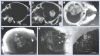

Materials & methods: Gold nanoparticles approximately 11 nm in size were injected intravenously and brains imaged using microcomputed tomography. A total of 15 h after an intravenous dose of 4 g Au/kg was administered, brains were irradiated with 30 Gy 100 kVp x-rays.

Results: Gold uptake gave a 19:1 tumor to normal brain ratio with 1.5% w/w gold in tumor, calculated to increase local radiation dose by approximately 300%. Mice receiving gold and radiation (30 Gy) demonstrated 50% long term (>1 year) tumor-free survival, whereas all mice receiving radiation only died.

Conclusion: Intravenously injected gold nanoparticles cross the blood-tumor barrier, but are largely blocked by the normal blood-brain barrier, enabling high-resolution computed tomography tumor imaging. Gold radiation enhancement significantly improved long-term survival compared with radiotherapy alone. This approach holds promise to improve therapy of human brain tumors and other cancers.